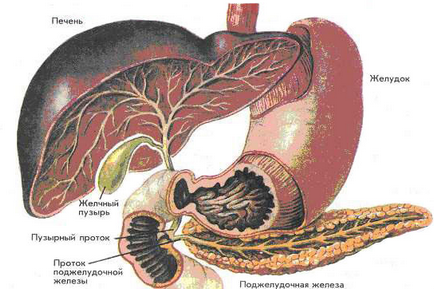

Sigilarea ficatului și pancreasului

ficatului și pancreasului Seal, ca un fel de tulburări ale tractului digestiv, este diagnosticat destul de dificil și, prin urmare, necesită intervenția unui gastroenterolog cu experiență. Principalele metode de investigare a acestor patologii sunt metoda chestionarului, examinarea cu raze X și intervenție instrument. În general, această formă a bolii este usor tratabile, dar există riscul unor complicații cauzate de fiziologia pacientului. Dacă apar complicații, pacientul ar trebui să caute ajutorul unui chirurg.

Motive pentru compactarea pancreasului

Identificarea unor astfel de modificări difuze pancreatice cum să sigileze, are loc de obicei prin intermediul unui tratament cu ultrasunete. Principalele cauze ale bolilor se află în funcționarea necorespunzătoare a sistemului endocrin și regimul alimentar neregulat al pacientului, dar există și cazuri individuale legate de moștenire sau funcționarea anormală a tractului gastro-intestinal. În acest caz și într-un alt, o decizie finală cu privire la apariția focilor pancreatice, poate lua numai un specialist cu experiență.